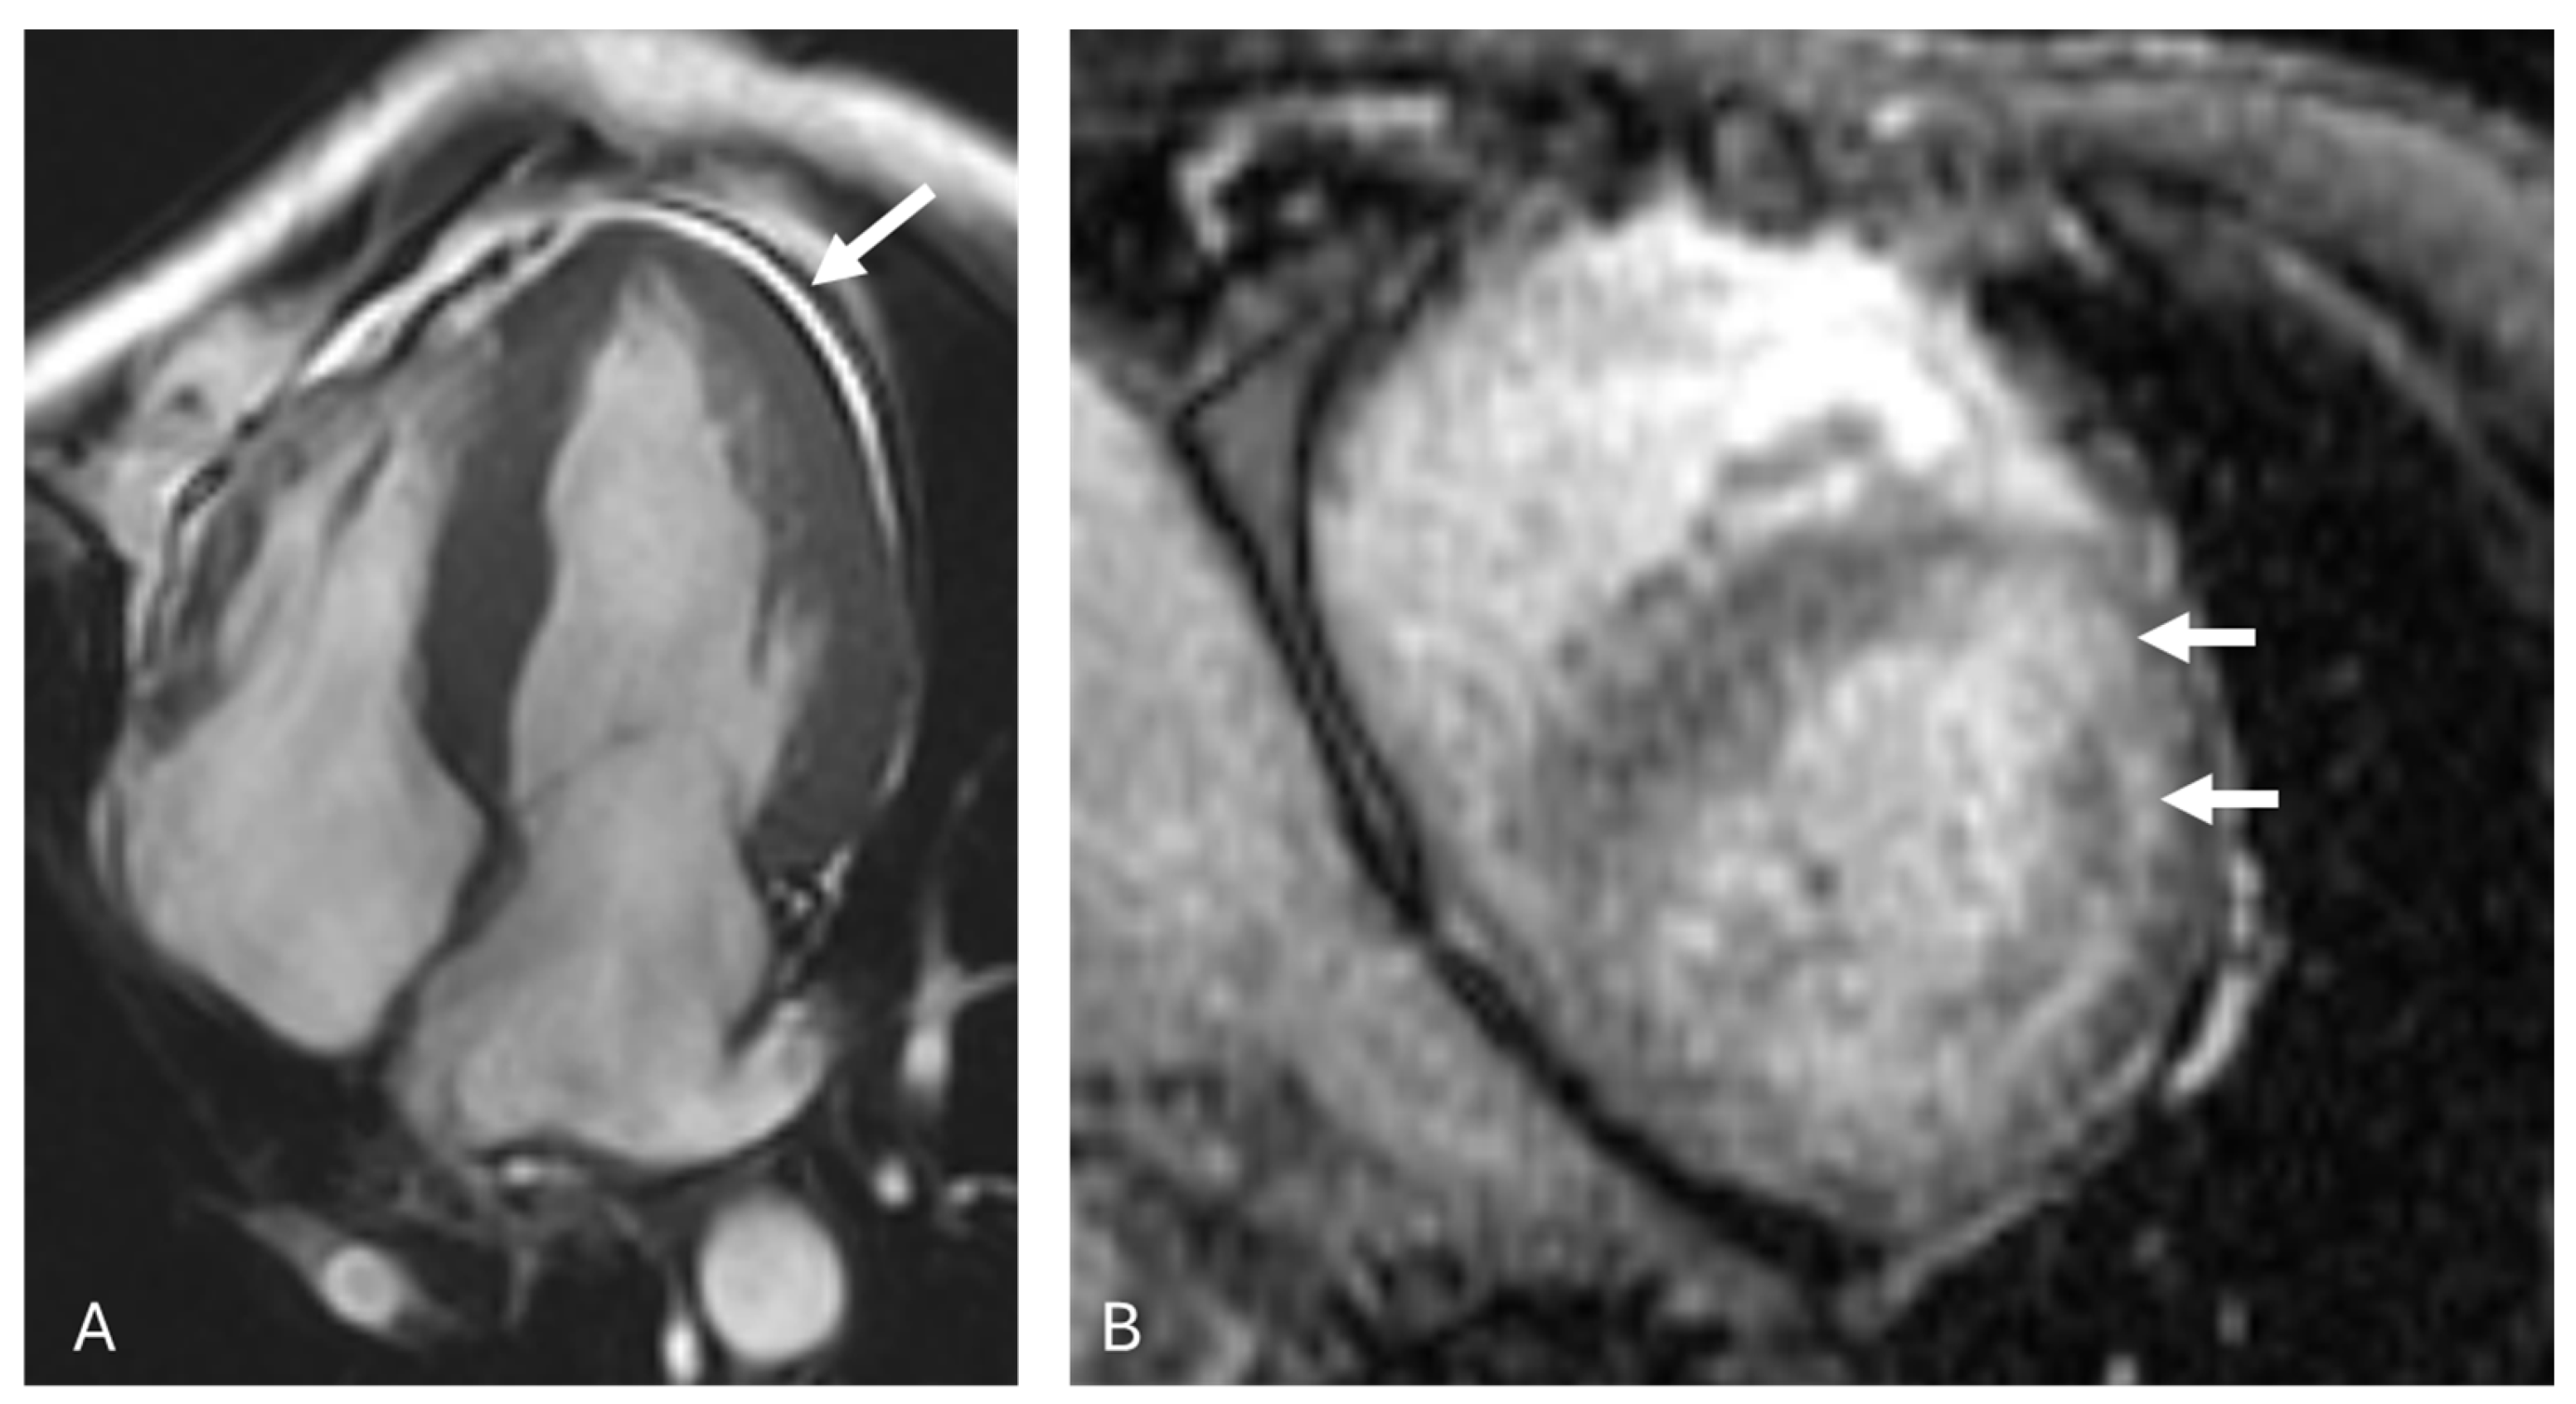

3.2. AL Amyloidosis